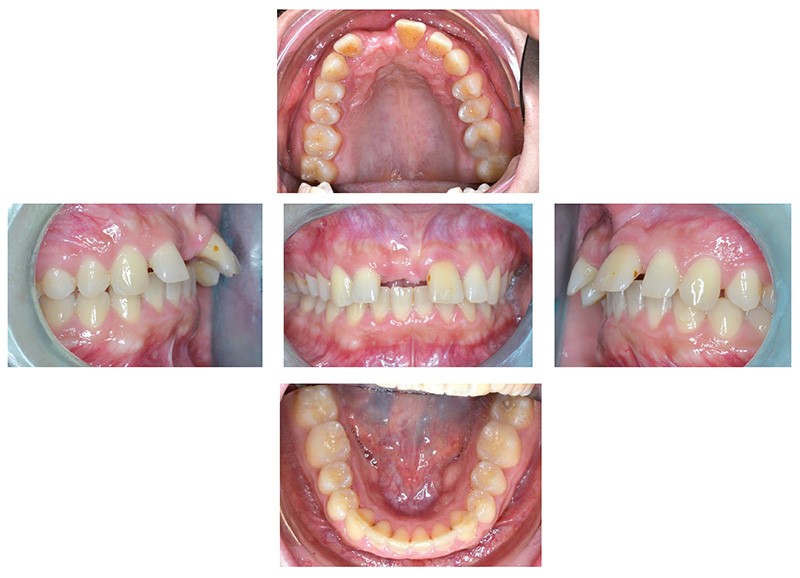

Il a été décidé de mettre en place un traitement ortho-chirurgical avec multi-attaches maxillaire et mandibulaire et avancée mandibulaire première (fig. 3a) [1]. Ce traitement est réalisé en technique d’arc droit avec des attaches vestibulaires informées en Roth en .022 x .028. Il durera quinze mois, pose d’implant comprise.

La patiente est appareillée une semaine avant la chirurgie d’avancée mandibulaire première sans mise en place de l’arc (Chirurgie réalisée par le Dr Laurentjoye). Dix jours après la chirurgie, les premiers arcs (.016 Niti) sont mis en place, avec l’utilisation de tractions intermaxillaires d’intercuspidation tendance classe II (fig. 3b). Après la réalisation du traitement et la mise en place d’une dent provisoire sur l’arc à la taille et la forme souhaitées…